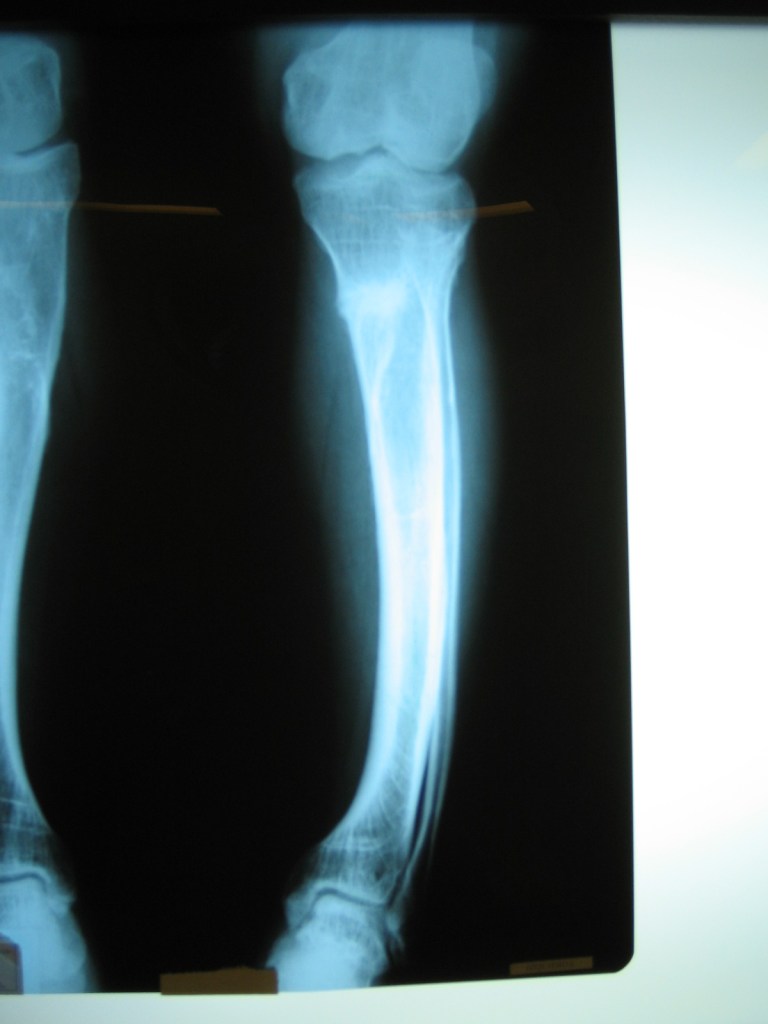

niño de 6 años con osmelitis en tibia

Luego de una fractura , mi hijo a los 6 años adquirió una infección ósea con exposición del hueso , que no podía tratarse en Chaco, por lo que tras una consulta con el Dr Dratewka , se explico las opciones de tratamiento

Luego de una 1 cirugía que consistió en remover todo el tejido muerto y acortar el hueso , pudimos tratar la infección ,y en una 2 cirugía alargar la pierna nuevamente

Hoy mi hijo ha podido volver a todas sus actividades